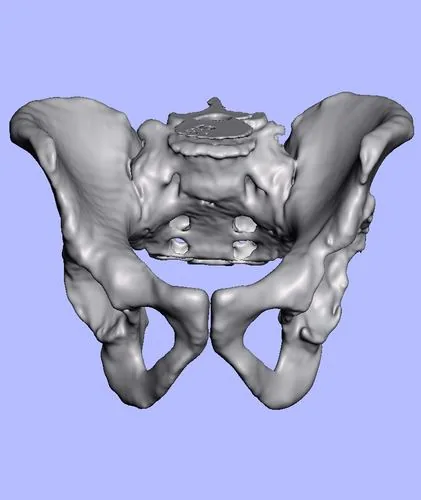

Planificación 3D con biomodelos

Utilizamos tecnología de impresión 3D para crear modelos exactos de tu anatomía antes de la cirugía. Esto nos permite planificar cada detalle con precisión milimétrica y reducir significativamente el tiempo quirúrgico.

Precisión milimétrica

Guías de corte personalizadas basadas en tu anatomía real.

Menor tiempo quirúrgico

La planificación previa reduce significativamente la duración de la cirugía.

Restauración del centro de rotación

Optimizamos el alineamiento del implante para mejor funcionalidad y duración.

Biomodelos impresos, segmentación digital y planificación 3D aplicada a cirugía de cadera

¿Qué es la planificación 3D con biomodelos en cirugía de cadera?

La planificación 3D con biomodelos es una tecnología de vanguardia que consiste en imprimir en 3D un modelo físico exacto de la cadera del paciente, obtenido a partir de una tomografía computada. Este modelo permite al cirujano planificar el procedimiento con una precisión que no es posible solo con imágenes digitales: se selecciona el implante ideal, se anticipa cada paso quirúrgico y se minimizan los imprevistos durante la operación.